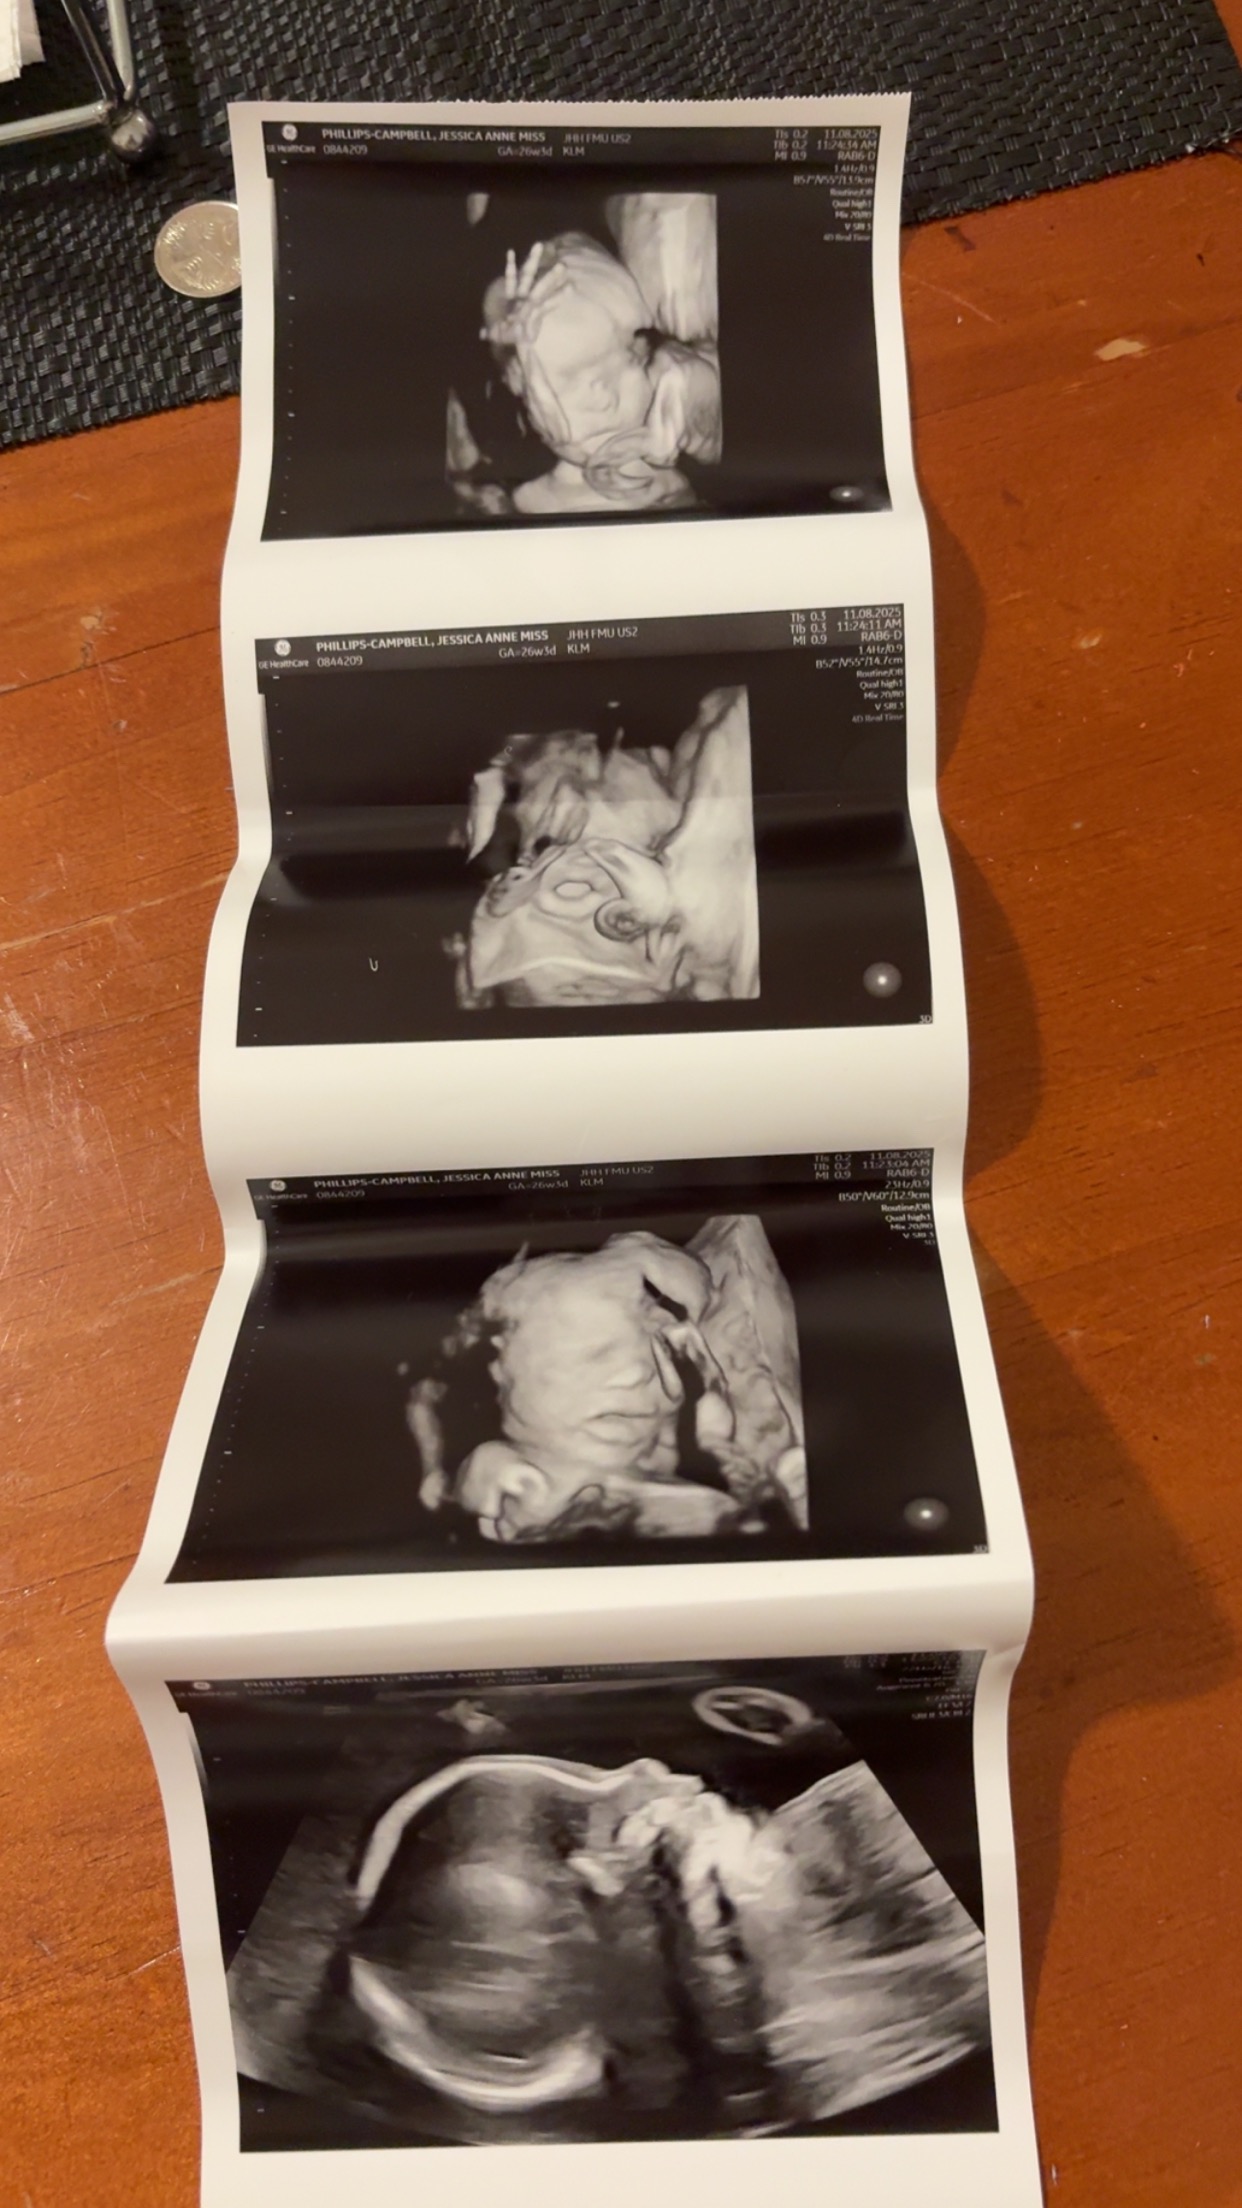

Hi, my name is Jess. I have my partner Jarrod & my beautiful son Jaxon. In March 2025, we found out we were expecting our beautiful girl Jayda Lavina Hickey in November 2025.

She had a lot of fluid on her brain. I went for a follow up scan 2 weeks later. We were told it was a possible stroke and brain bleed. They offered us termination. We didn’t go through with it, we went with more tests to get down to what exactly happened, what the outcome would be & possibly find out what caused it.

The MRI confirmed it all.. but no cause.

My baby girl has agenesis of the corpus callosum, a piece of her brain didn’t develop and she has a blockage in her brain which can’t drain the fluid and blood.

Unfortunately due to this, she has no survival rate.

I can go full term but there is a very high chance she will pass.

I will be getting induced on the 18/08/25 to give birth to her & she will be placed in palliative care and will die within hours of being born, in either her mums or dads arms.